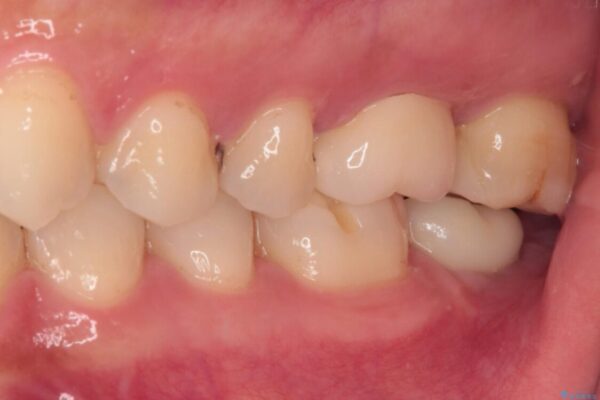

奥歯がズキズキと痛み、食事で噛むことができないとのことで来院された患者様です。 以前治療を受けたとき、むし歯が大きかったため、神経組織が炎症を起こす可能性があると指摘をされていたとのことでした。

治療前

• 奥歯がズキズキと痛む 奥歯の虫歯治療 治療前画像